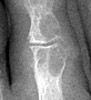

RA Rheumatoid Arthritis: Marginal erosions at 1st IP joint

++